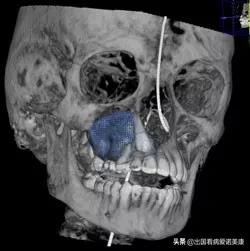

口腔右侧顶部的肿瘤范围(以蓝色突出显示)

但是在达米恩11岁那年,他平静的生活被打破了。2018年4月,他被诊断为颌面部肿瘤,这个肿瘤呈柠檬状,位置特殊。

2018年12月,辛辛那提儿童医院为达米恩进行了活检,显示肿瘤是非癌性的。但是因为考虑到肿瘤的大小,其导致面部畸形和癌变的可能性很高,他的医疗团队还是建议他尽快进行手术。

肿瘤过大,位置特殊,是对辛辛那提医疗团队的一个严峻的考验,手术过程的每一步的操作不当都有可能导致达米恩面部畸形。鉴于肿瘤的复杂性,正常情况下达米恩可能要进行不止一次的手术,包括前期的肿瘤切除和后续的放射治疗在内,连续好几天,达米恩可能会进行反复的手术,这对一个11岁的孩子来说是一个非常大的挑战。